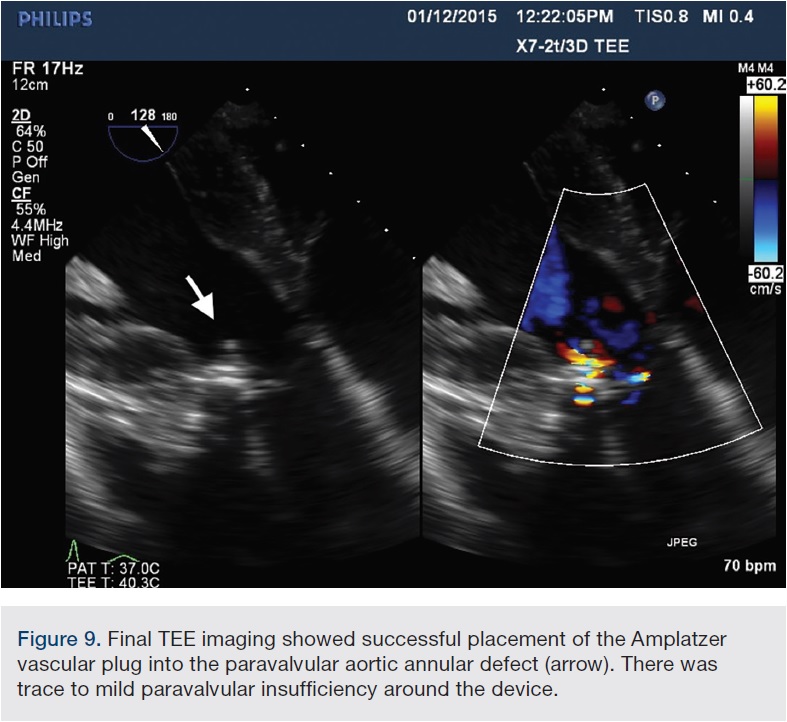

The procedure was performed under deep sedation with use of intravenous (IV) propofol. Transesophageal echocardiography (TEE) was utilized to assist in the closure of the aortic paravalvular leak (PVL). TEE confirmed a bioprosthetic aortic valve with mild central intrinsic regurgitation, and moderate to severe paravalvular regurgitation (Figure 1A-B). The paravalvular regurgitation was found at the lateral aspect of the aortic annulus (Figure 2).

At this point, the approach was changed. The Extra Back-Up (EBU) 3.5 guide was advanced from the femoral approach to selectively engage the left main ostium. The EBU guide was left in place to protect the left main ostia, because the paravalvular leak was closed to the left main origin. Using a 5 French JR4 guide catheter via the right radial access, we were able to successfully advance the JR4 guide catheter through the paravalvular leak (Figure 5). A 5 French, 90cm Destination sheath was telescoped over the 5 French guide catheter across the PVL. Under TEE and fluoroscopic guidance, an 8mm Amplatzer Vascular Plug (St. Jude Medical) was deployed across the PVL and through the Destination sheath, and a tug test was performed. (Figure 6A-B, 7). The final TEE imaging showed a well-deployed Amplatzer Vascular Plug into the paravalvular aortic annular defect, with a significant decrease in paravalvular regurgitation compared with the pre-procedure study (Figures 8, 9). A trace to mild paravalvular insufficiency and a mild intrinsic central aortic insufficiency were seen (Figure 10). A hemostatic band and a vascular closure device were used to achieve hemostasis in the radial artery and femoral artery, respectively. The patient tolerated the procedure well and she was discharged from the hospital the next morning. At her follow-up visit, she had significant improvement in her symptoms.